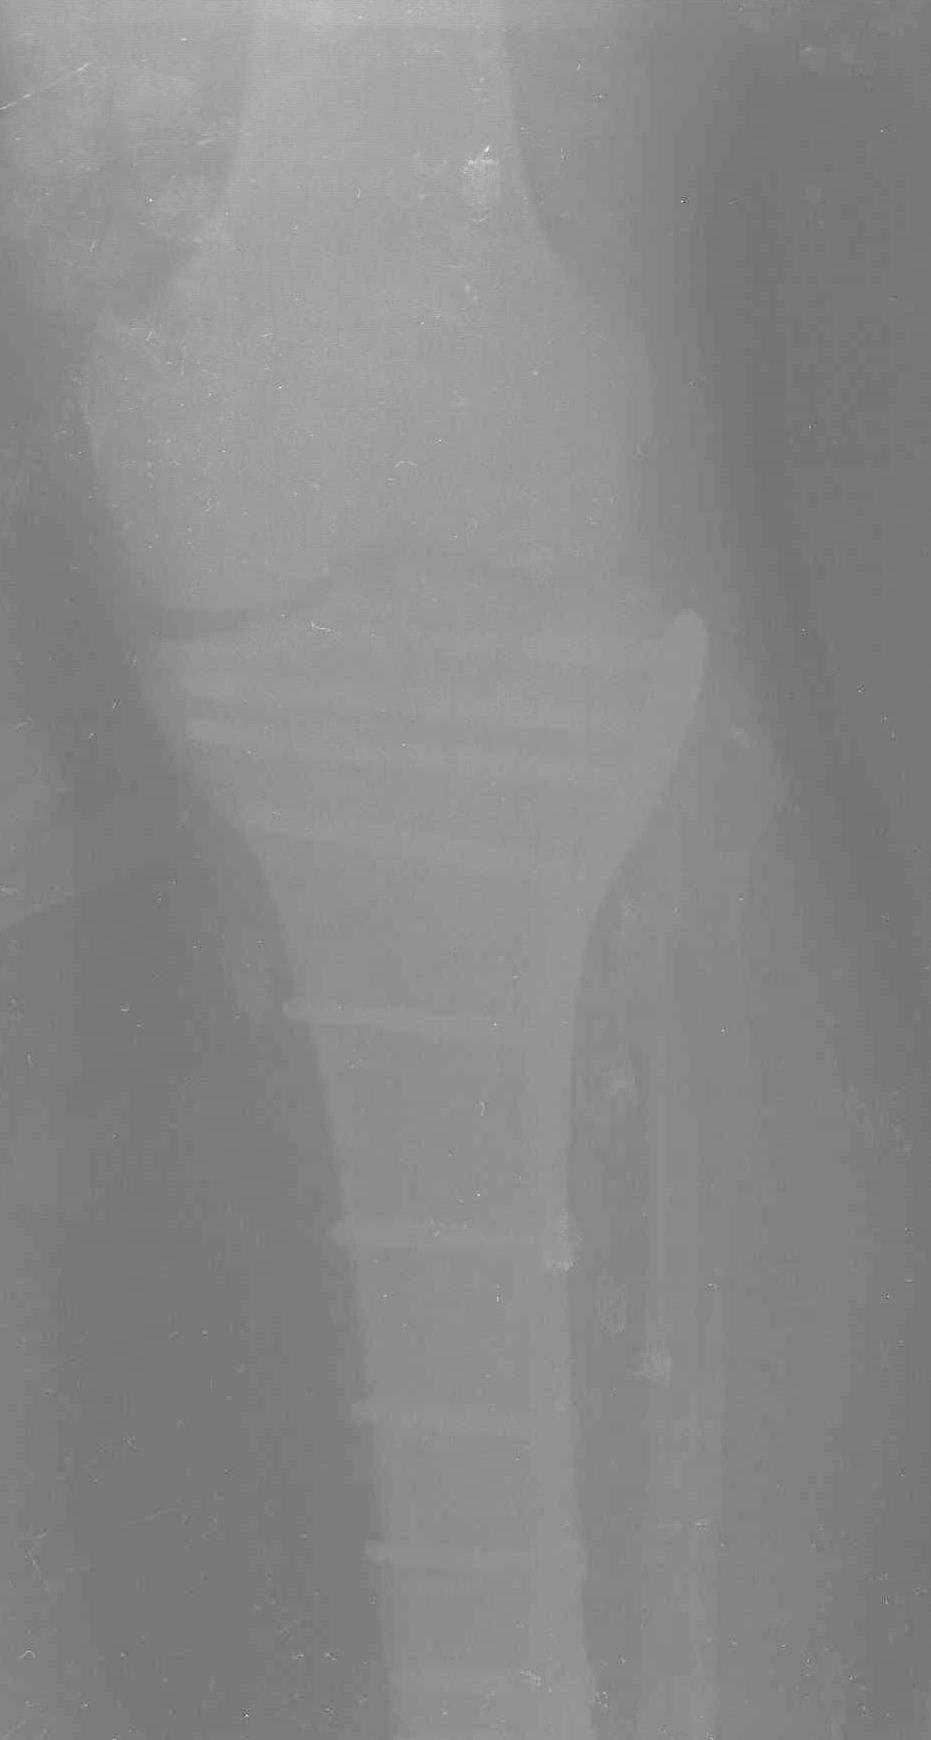

На представленных предоперационных срезах КТ огромный задне-медиальный фрагмент расположен больше кзади, чем медиально. Для планирования, кроме поперечных срезов, надо ориентироваться на корональные срезы, которые укажут топографию верхушки медиального фрагмента.

При сложных переломах тибиал плато для своего рода Damage Control мы иногда применяем поэтапную тактику. Сперва оперируется одна сторона, а потом после рекондиции мягких тканей окончательный этап.

Если состояние мягких тканей позволяет, я бы предложил такой метод для вашего больного. Без предварительного планирования будет трудно, но шанс не надо упускать. Всего несколько дней после операции, и такая тактика лучше, чем недовольный молодой пациент.

Доступ к медиальной стороне задний или медиальный, через pes или в пространстве между medial gastroc мышцы.

Надеюсь, представленные снимки разных случаев помогут разобраться в тактике, и критика примется без личной обиды.